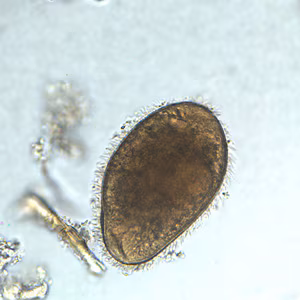

A 45-year-old pig farmer from rural Georgia presented to his health care provider with abdominal pain, cramps and diarrhea. Stool specimens were collected in polyvinyl alcohol (PVA) and 10% formalin for ova and parasite (O&P) examination. The objects in Figures A and B, which measured on average 90 micrometers in length, were observed in low numbers in formalin-concentrated wet mounts of the stool. The objects in Figures C and D, which measured on average 12 micrometers in diameter, were seen in moderate numbers on trichrome-stained slides prepared from the PVA-preserved stool. What is your diagnosis? Based on what criteria?

Figure B